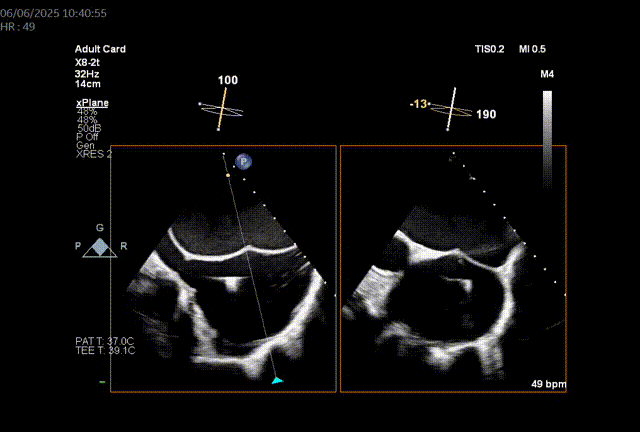

由于二尖瓣环和主动脉瓣角度过大,若采取经心尖方式,同轴性不佳,且难以调整定位件,同样采取经房间隔方式。